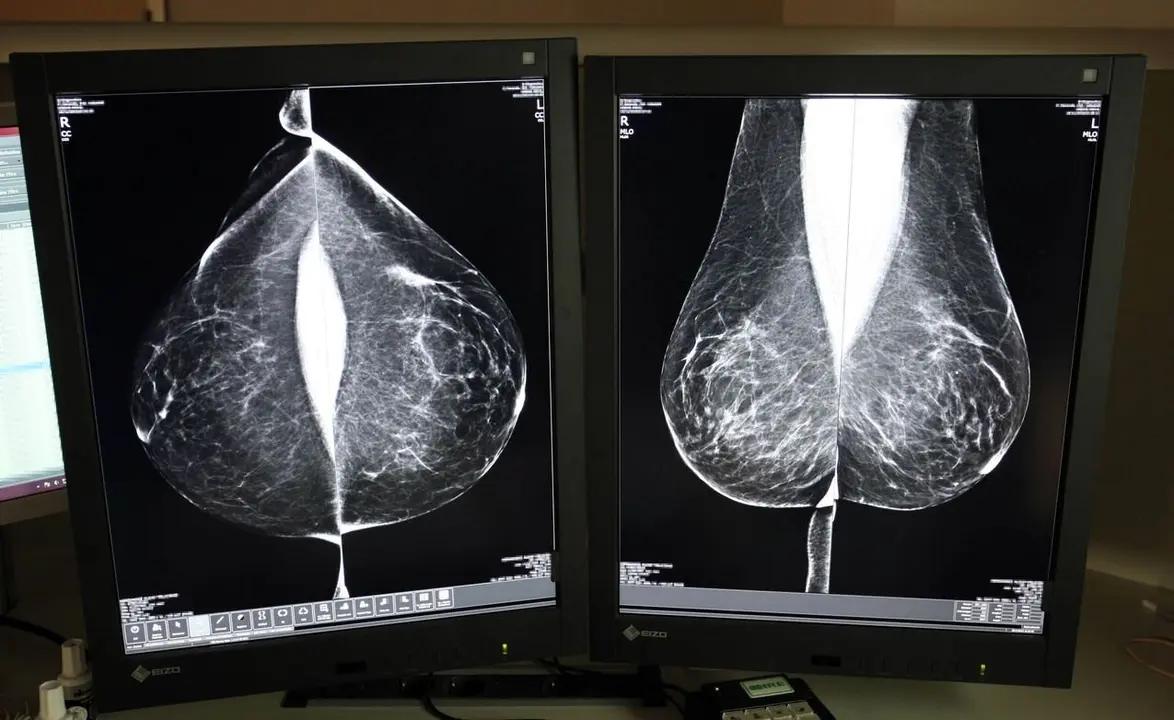

Desde su puesta en marcha en 1992, el programa se basa en el sistema de doble lectura, un protocolo que establece que cada mamografía sea evaluada por al menos dos radiólogos, de forma independiente, aumentando así la fiabilidad de los diagnósticos. Sin embargo, aumenta la carga de trabajo y plazos, motivo por el cual Sacyl ha optado, de nuevo, por externalizar el servicio al que el año pasado dedicó casi cuatro millones.

De forma paralela, la Gerencia Regional de Salud trabaja ya en la incorporación de un sistema de lectura con inteligencia artificial (IA) que podría implantarse en diciembre. Este software, que supondrá una inversión de 1,32 millones de euros financiada íntegramente con fondos europeos NextGeneration EU, permitirá a los profesionales sanitarios mejorar la precisión diagnóstica, reducir los tiempos de lectura y priorizar casos sospechosos mediante algoritmos certificados con marcado CE.